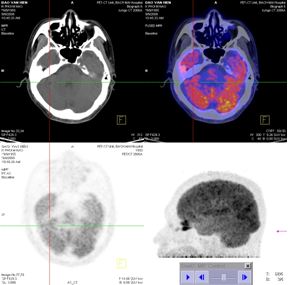

PET/CT

Kết quả: Thành ngực, trung thất và nhu mô phổi 2 bên và các tổ chức ngoài não khác không thấy có hấp thu F-18 FDG bất thường.

1. Tại não

· Khối u đã thu nhỏ kích thước (từ 33mm xuống còn 14mm), tổ chức khối u thoái hoá dạng nang (trên PET/CT, max SUV=3,54)

· Không có tổn thương mới

2. Tại phổi

· Khối u tan hoàn toàn

· Không xuất hiện tổn khác tại phổi và ngoài phổi